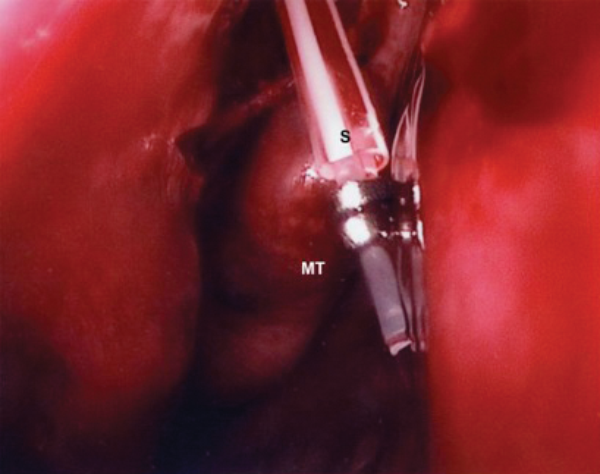

MT - Middle Turbinate S - Stents

Figure 9a (top) & 9b (above). Stent stabilisation with Ligaclips.